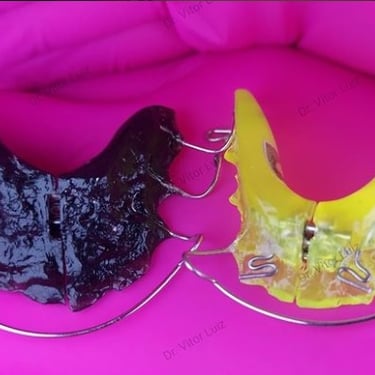

Aparelho ortodôntico